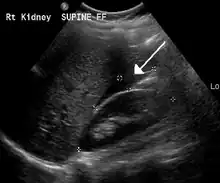

The use of ultrasound has become the standard of care when preparing a patient for paracentesis. Confirmation of an ascitic effusion reduces the risks associated with a dry or blind tap of the abdomen. Anatomic landmarks, such as the midline linea alba approach, were traditionally used as reference points for needle insertion. Phased array or curvilinear ultrasound transducers are typically used in the hospital and outpatient setting to identify ascites in the abdominal cavity. Fluid within the abdominal cavity appears hypoechoic or anechoic (black) on ultrasound. Morison's pouch (hepatorenal recess) is a common starting location in concordance with ultrasound FAST (focused assessment with sonography for trauma) exam. Fluid collection can occur in a number of different locations and may be difficult to find, especially if the patient only exhibits a small volume of ascites. Measurement of the amount of fluid within the abdominal cavity is not necessary or very successful. Identification of sufficient fluid within the abdominal cavity for fluid analysis or to achieve a therapeutic benefit is all that is required to proceed to paracentesis. Ultrasound guidance of the paracentesis can also be used as an additional safety measure to ensure the needle stays within the ascitic fluid and avoidance of important vessels within the abdominal cavity. [5]

Small fluid collection in Morison's pouch